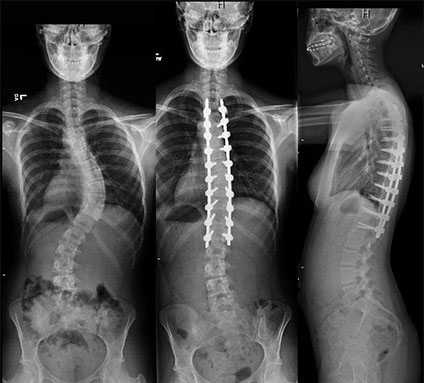

Scoliosis

کژ پشتی یا اسکولیوز به انحراف جانبی ستون مهره ها به سمت راست یا چپ که علت مادرزادی یا اسکولیوز اکتسابی است، راشیتیسم یا نرمی استخوان میگویند. اسکولیوز یا کژ پشتی بسته به نوع آن ، میزان ایجاد انحراف سن بیمار و موارد دیگر به وسایل کمک یا فیزیوتراپی یا عمل جراحی نیاز دارد.